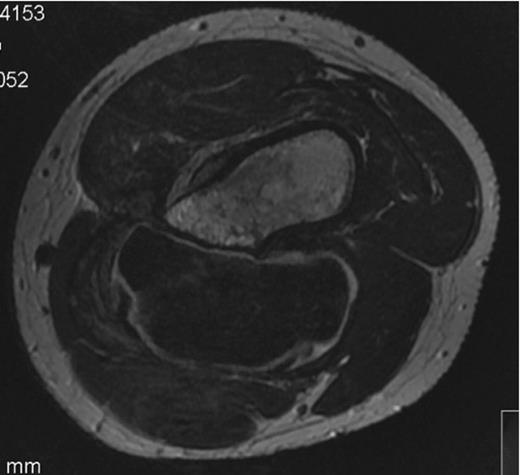

The MRI scan showed a lesion measuring 9.5cm in its greatest diameter, of uniform signal, with a cartilage cap exceeding 2cm throughout most of its surface. (Figure 2)